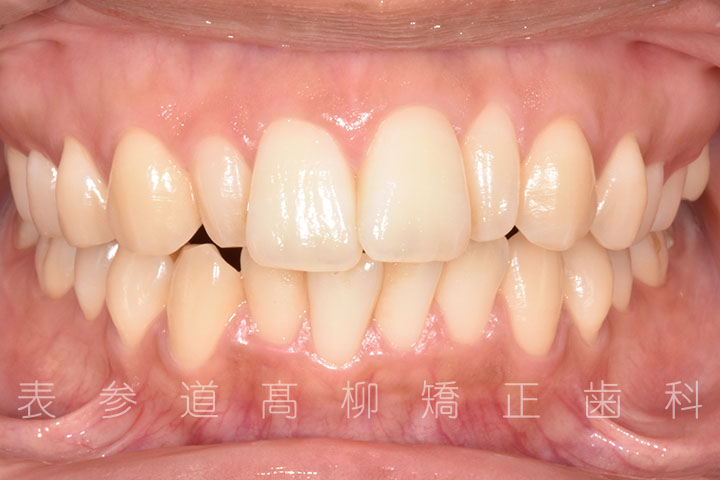

・矯正治療終了後 加部歯科医院(https://kabe-dent.net) にて2⏊2補綴処置を行った

術前術後の比較